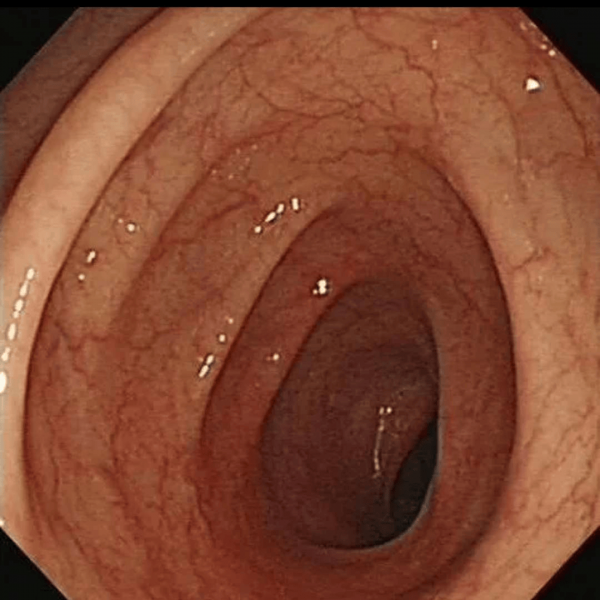

(正常肠道vs失去弹性的肠道)